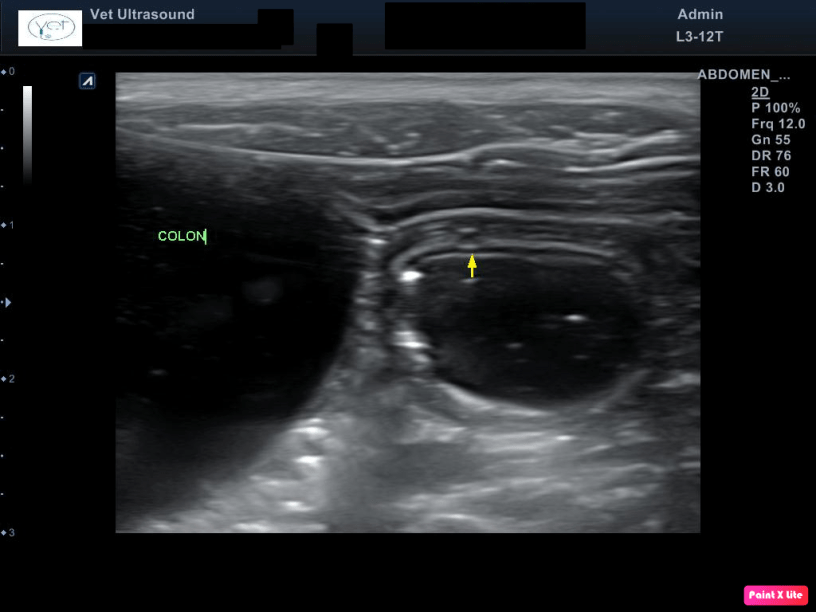

Το παχύ έντερο ήταν διατεταμένο με άνηχο υγρό περιεχόμενο και αέρα. Στον υποβλεννογόνιο χιτώνα βρέθηκαν υπόηχα οζίδια λίγων χιλιοστών.

Έχει αναφερθεί στην βιβλιογραφία πως η παρουσία υπόηχων οζιδίων στον υποβλεννογόνιο χιτώνα του παχέος εντέρου πιθανά οφείλεται σε αντιδραστική διόγκωση των λεμφικών κέντρων.